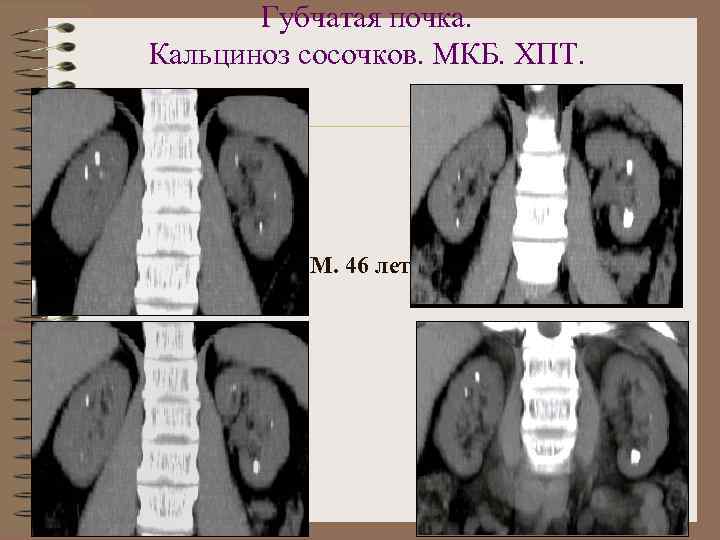

Губчатая (микрокистозная) почка • Вариант тубулярной дисплазии • Дилатация прямых канальцев с образованием множественных псевдокист • Расширенные канальцы выстланы однослойным кубическим эпителием • Кальциноз стенок канальцев и периканаликулярной ткани • Осложнение - МКБ • Процесс всегда 2 -сторонний • Чаще болеют мужчины

Признаки губчатой почки • Увеличение размера почек • Увеличение размера пирамид и уменьшение – коркового слоя • Гиперэхогенные пирамиды при УЗИ • Множественные мелкие конкременты в мозговом слое • Кальциноз сосочков пирамид • В/в урография - пирамиды неравномерно контрастированы ( «букет сирени» , «салют» )

Губчатая почка

Р-признаки губчатой почки Обзорная рентгенограмма ВВ урография

Губчатая почка. Кальциноз сосочков. МКБ. ХПТ. М. 46 лет